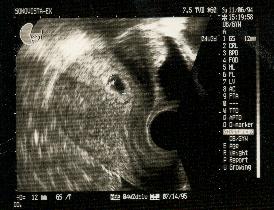

はじめての経膣超音波 (妊娠4周〜5週) : 当院ではほぼすべて超音波は妊婦さんにもお見せします。

あかちゃんのはいる袋(胎嚢)の確認。

胎嚢の大きさは12mm(子宮の中にちゃんと着床しているかの確認)。